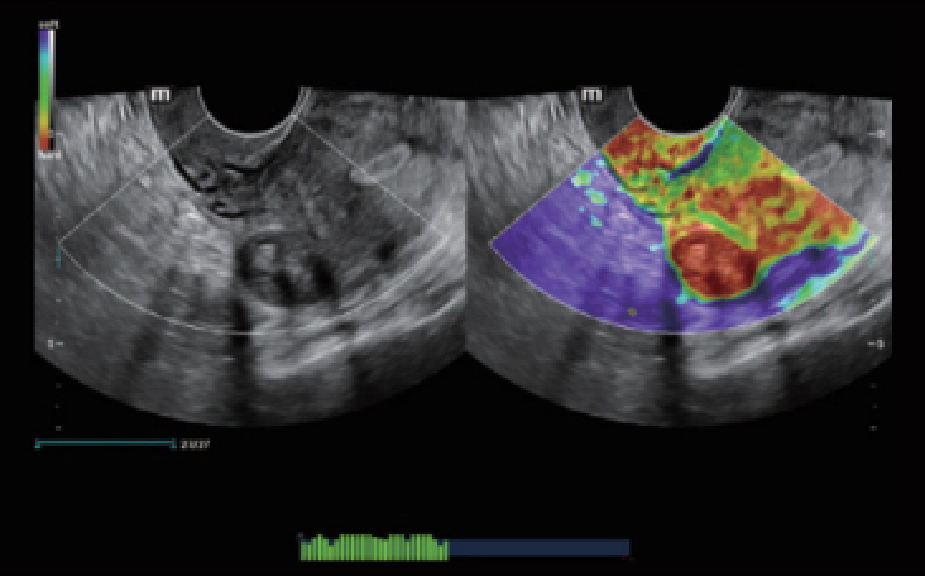

Clinical Images